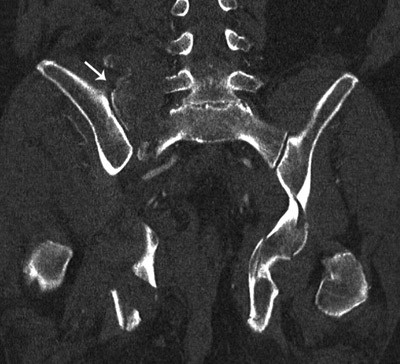

CT-undersøkelsene, som ble gjort omtrent to timer etter innkomst, avkreftet aortaaneurisme og alvorlig sykdom i hodet. Det var basale fortetninger i begge lunger. CT-undersøkelse av bekkenet viste multiple frakturer (fig 1, fig 2). På høyre side var det knusing av massa lateralis sacrii og en fraktur av fremre bekkenring med flere små fragmenter. På venstre side var femur trykt inn i bekkenet med en knusingsfraktur i acetabulum. Det var væske retroperitonealt og i muskulaturen i bekkenet. Mengden kunne ikke angis eksakt. På grunn av pasientens fallende blodtrykk og økende puls ble det startet kontinuerlig infusjon med noradrenalin i tillegg til pågående væskeinfusjon.

Ved ny klinisk undersøkelse viste det seg at smertene var lokalisert mer til bekkenregionen enn til ryggen. Pasienten var hemodynamisk ustabil, bekkenfrakturen var ustabil, og i tillegg var det acetabularfraktur. Bekkenfrakturen var den sannsynlige blødningskilde. Ortopedene bestemte seg derfor for å stabilisere frakturene med ekstern fiksasjon.